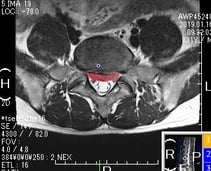

椎間板ヘルニア

2年前から腰痛を感じ少しずつ悪化、1年前に整形外科を受診し、MRI検査で椎間板ヘルニアと診断される。

関節調整・スーパーライザーにてヘルニア該当部位への組織の治癒過程の促進, 炎症の鎮静や微細循環の促進,浮腫の改善・